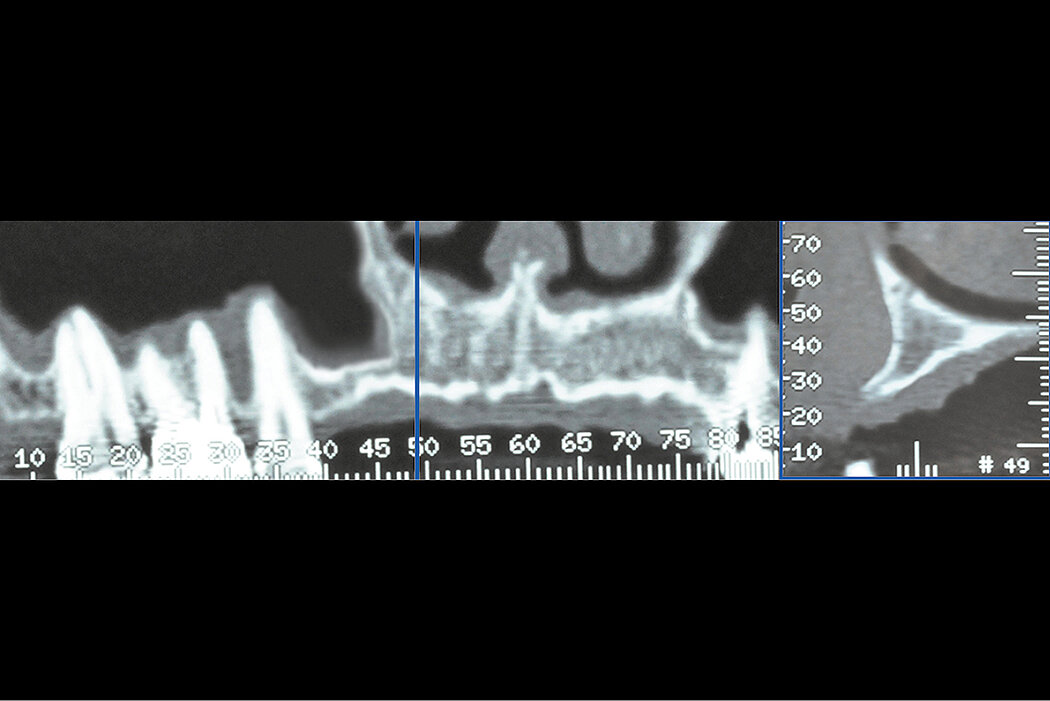

A 62-year-old female healthy patient was referred to the Schwartz-Arad surgical center for an extraction of the first right maxillary molar. This clinical case was performed in 1997 with a 20-year follow-up period. The region of interest is the right maxillary molar. In this region the 1st right maxillary molar was untreatable due to a perio-endo defect. The first and second right maxillary premolars were missing as well. The existing bridge included the right maxillary canine and the first molar. The available alveolar ridge was not sufficient for implant placement due to the pneumatization of the right maxillary sinus and the endo-perio-lesion of the tooth. The patient came for a treatment to obtain a fixed prosthetic restoration. The clinical challenge was to simultaneously reconstruct the ridge volume in the vertical dimension via a sinus augmentation procedure, and ridge preservation at the time of tooth extraction, for second stage implants placement.

Prophylactic oral pre-medication of amoxicillin (1g) and dexamethasone (8mg) an hour before the procedure and a local application of 0.5% chlorhexidine for 2min. An incision was made on the alveolar crest and a vertical incision distal to the tuberosity was made to allow bone harvesting from this area to be mixed with the Geistlich Bio-Oss® . A window was cut through the lateral sinus wall cortex using a slow-speed round bone bur. At this point, the sinus membrane was carefully elevated from the sinus floor and medial sinus wall. Geistlich Bio-Gide® was used to repair the perforation. Since primary implant stability could not be attained, a delayed 2-stage implant placement was performed 5 months later. The maxillary sinus compartment was augmented with Geistlich Bio-Oss®. The fenestrated lateral wall of the maxillary sinus was covered with a Geistlich Bio-Gide® and the mucoperiosteal flap repositioned and sutured with a 3/0 Vicryl.